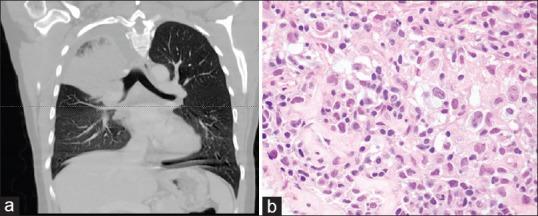

Pulmonary lymphoproliferative neoplasms are rare lung tumors and account for <1% of all lung tumors. Among them, primary pulmonary lymphomas (PPL) constitute the majority, which include Non-Hodgkin's lymphoma (NHL) that comprise of mucosa-associated lymphoid tissue lymphoma, diffuse large B-cell lymphomas and other rare types of NHL and lymphomatoid granulomatosis. HL, which arises secondary to contiguous spread from the mediastinum, is the rarest type of PPL. Other entities described within the umbrella of pulmonary lymphoproliferative neoplasms include pleural lymphomas and posttransplant lymphoproliferative disorders (PTLD) - which occurs in the poststem cell and organ transplant patients. These neoplasms although rare, have a favorable prognosis, which does not depend on disease resectability. Moreover, with its nonspecific presentation, diagnosis is challenging, which often leads to delayed diagnosis or misdiagnosis in many cases. Therefore, knowledge of this entity is important for the practicing pulmonologist. This review article aims to describe the clinical presentation, diagnosis and management of primarily the entities within PPL, as well as pleural lymphomas and PTLD.

肺淋巴增殖性肿瘤是罕见的肺部肿瘤,占所有肺部肿瘤的比例不到1%。其中,原发性肺淋巴瘤(PPL)占大多数,包括非霍奇金淋巴瘤(NHL),后者由黏膜相关淋巴组织淋巴瘤、弥漫性大B细胞淋巴瘤以及其他罕见类型的NHL和淋巴瘤样肉芽肿组成。HL是PPL中最罕见的类型,它继发于纵隔的连续性扩散。肺淋巴增殖性肿瘤范畴内描述的其他实体包括胸膜淋巴瘤和移植后淋巴增殖性疾病(PTLD)——发生于干细胞和器官移植后的患者。这些肿瘤虽然罕见,但预后良好,其预后并不取决于疾病的可切除性。此外,由于其表现不具有特异性,诊断具有挑战性,这在许多情况下常常导致诊断延迟或误诊。因此,了解这一实体对执业肺科医生很重要。这篇综述文章旨在描述主要是PPL内的实体以及胸膜淋巴瘤和PTLD的临床表现、诊断和管理。